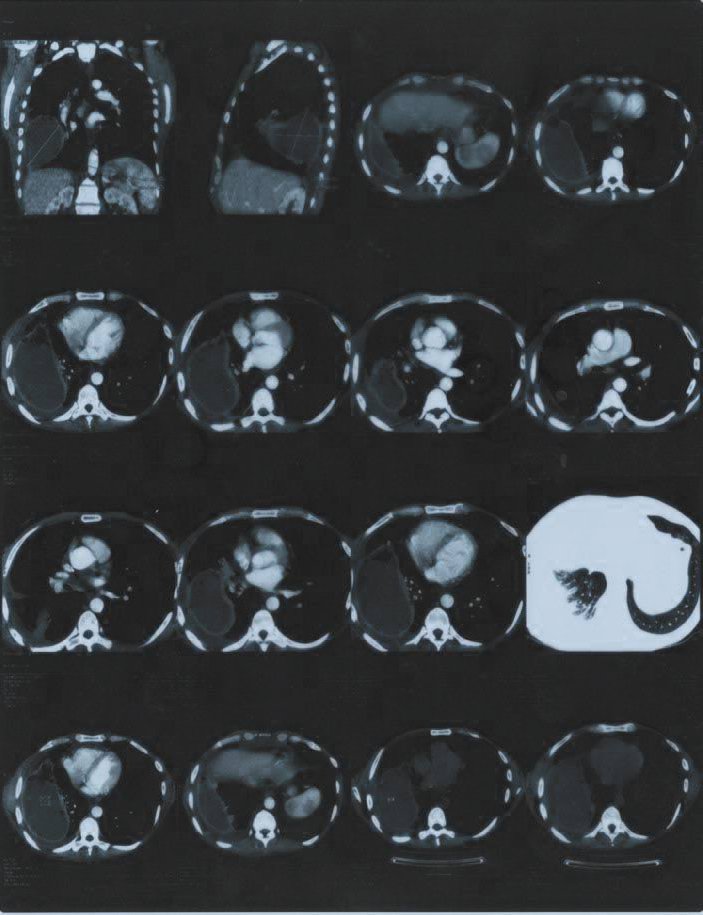

Так или иначе состояние улучшилось настолько, что у меня хватило физических сил наконец-то пройти полное медицинское обследование. Результаты были удручающими, первый же рентгеновский снимок (рис. 1) показал наличие опухоли в лёгком размером с грейпфрут, последующая компьютерная томография показало эту опухоль уже во всей красе (рис. 2). Помимо опухоли, на снимках видно, что заболеванием была полностью затронута печень, именно поэтому организм перестал принимать и перерабатывать пищу. Врачи в один голос требовали срочного оперативного вмешательства. Был поставлен предварительный диагноз – рак, для подтверждения, которого необходимо было провести биопсию, от которой я отказался. Кроме того, мой отказ был мотивирован еще и тем, что вопреки всем исследованиям, по личным ощущениям моё состояние с каждым днем становилось всё лучше.

В феврале 2016 был сделан контрольный снимок (рис. 3). Результат был поразительным, от опухоли не осталось и следа, осталась только соединительная ткань на стенке легкого, на снимке она видна как еле заметная пелена.

И вот ровно через год после первого снимка контрольный снимок показал абсолютно здоровые легкие, без каких бы то ни было следов перенесенной болезни (рис. 4).